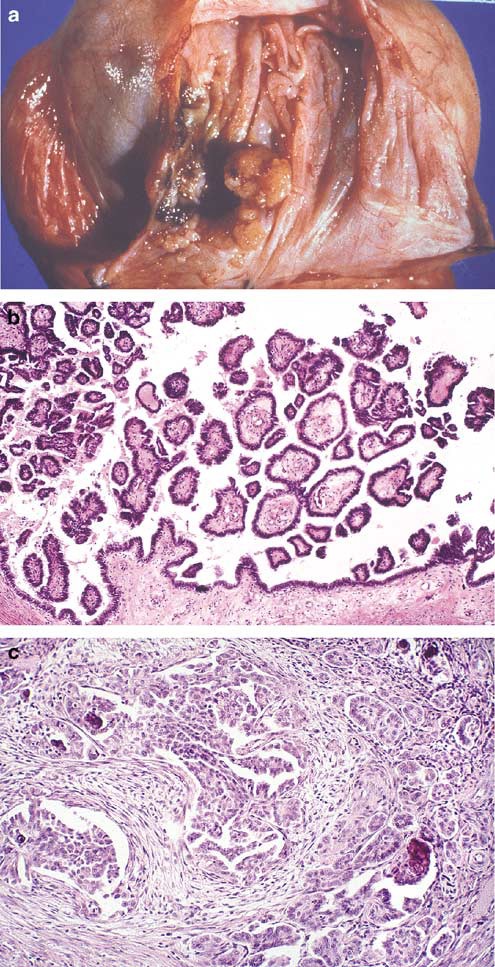

Gross examination reveals various appearances ranging from diffuse thickening of the tunica vaginalis or multiple nodules on it, sometimes coating it (Figure 10a, b). Infiltration of the testis, epididymis or cord structures is frequent. Microscopically, the tumors resemble their pleural and intra-abdominal peritoneal counterparts. Pure epithelial (60–70%) (Figure 10c) or biphasic (30–40%) (Figure 10d) histology is most frequently observed, but very rarely pure sarcomatous histology, including the desmoplastic variant, may be seen (Figure 10e).1, 24, 30 The entire spectrum of differentiation from well-differentiated tumors (tubulopapillary architecture, simple to typically more complex arborizing fibrovascular cores lined by a single layer or multilayered mildly atypical mesothelial cells, and variably invasive tubules) to poorly differentiated tumors (solid sheets, cords and nests of highly infiltrative epithelioid cells with necrosis) may be seen. Foam cells, psammoma bodies and wide variation in glandular patterns (small tubules, irregular slit-like anastomosing channels and large glands and cysts with intracystic proliferation) may be present, compounding the histologic overlap with several other tumors that occur in the region. Focal areas may resemble an adenomatoid tumor. Careful gross examination, targeted sampling of tumor/tunica vaginalis interface and extensive sectioning may reveal transitions from normal to hyperplasia to invasive malignancy (Figure 10c). The tumor may invade paratesticular soft tissue, skin of the penis, scrotum or the testis, where it may occasionally have an intratubular pattern of growth. The differential diagnosis includes, at the well-differentiated end, mesothelial hyperplasia (discussed previously) and tumors with glandular architecture (discussed in the differential diagnosis of rete testis adenocarcinoma and summarized in Table 4). Tumors with spindle cell morphology may mimic sarcomas, and those composed of solid sheets of epithelioid cells may have a broad differential diagnosis with a number of malignant epithelial tumors and metastatic malignant melanoma. Immunohistochemistry, and even occasionally electron microscopy, may play a major role in the spindle cell and extensively epithelioid tumors, but thorough sampling is even more important.

Malignant mesothelioma of paratestis. Extensive nodular tumefaction of entire tunica vaginalis (a). Diffuse thickening of the tunica vaginalis with multiple nodules (b). Pure epithelial histology. Transition of tumor from more normal appearing tunica vaginalis is a useful diagnostic clue (c). Malignant mesothelioma with biphasic histology (d). Desmoplastic variant of malignant mesothelioma (e). (Figure b and e courtesy Dr Robert H Young, Boston, MA, USA.)